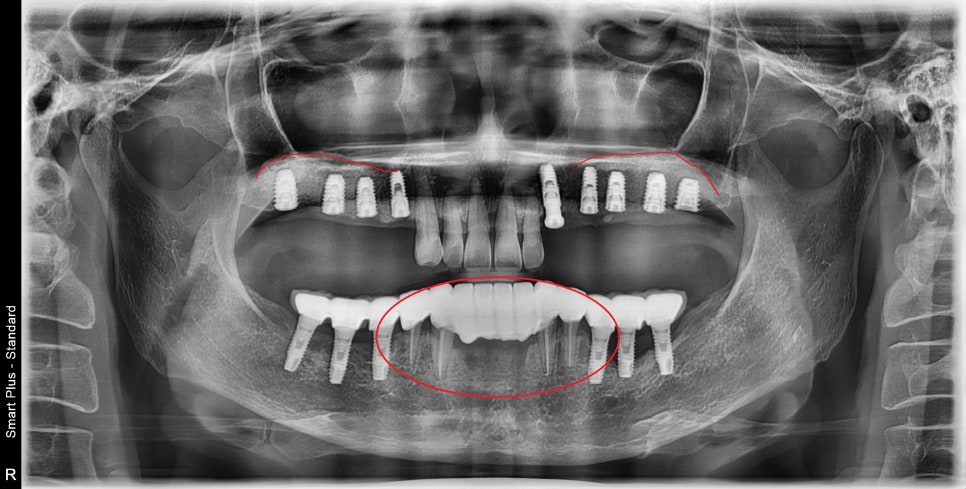

다수의 임플란트 식립 시 내비게이션 사용 / 광범위한 골이식 증례

양쪽 어금니가 발치된 지 오래된 상태셨고

위턱뼈의 뼈가 임플란트를 식립하기에는

너무 얇은 상태였습니다.

아래 앞니들은 치주염으로 인한 발치가 필요한 상황이며

위 앞니는 무너진 교합 때문에

앞으로 튀어나고 벌어져 있었습니다.

뼈가 너무 얇지만 광범위한 뼈이식 동시에

임플란트까지 식립하는 것을 목표로 하고

수술시간 단축을 위해 3D 내비게이션 가이드를 제작했습니다.

다행히 골이식과 동시에 임플란트를 수술 성공하였습니다.